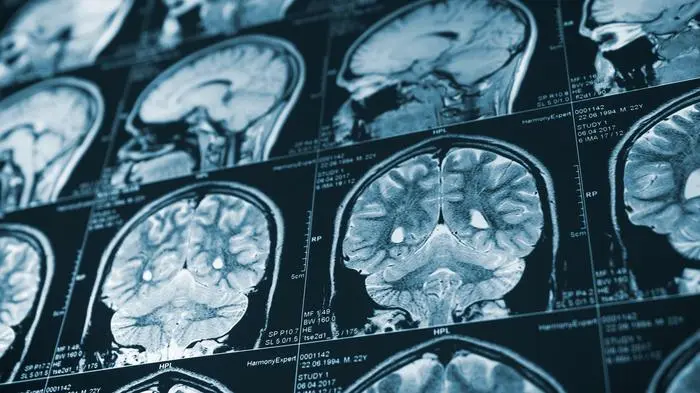

Neuer CT-Scanner erkennt "Mini-Thrombosen" – auch bei Long Covid

Ein hochauflösender CT-Scanner ist sogenannten Micro-Clots auf der Spur. Dabei handelt es sich – vereinfacht gesagt – um Mini-Thrombosen. Diese dürften auch bei Long Covid eine Rolle spielen.